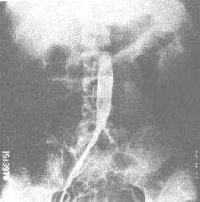

2.血管造影:

(l)管腔粗细不均、边缘比较光滑的向心性动脉狭窄和阻塞。

(2)动脉扩张动脉瘤形成。

(3)以腹主动脉、胸降主动脉、锁骨下动脉肾动脉为其好发部位。主动脉分支病变多累及开口部或近心段,局限性狭窄、阻塞多见。侵犯主动脉的狭窄,病变多较广泛。

(4)本病常为多发病变,可表现为不同组合。